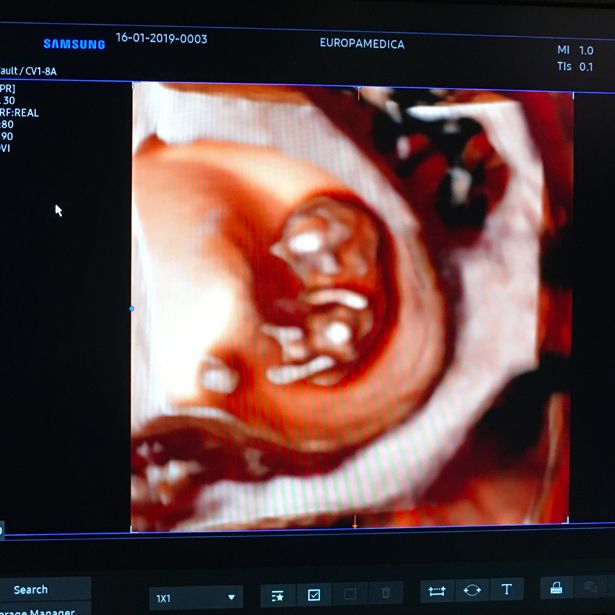

Ecografia 4D

L’ecografia 4D rappresenta un innalzamento qualitativo, rispetto alle ecografia tradizionale 2D. Grazie alla straordinaria qualità delle immagini delle tecnologie in dotazione (come l'ECO 4D Samsung HS40), il Dott. Luciano Di Leo sarà in grado di osservare il bimbo muoversi in tempo reale e di acquisire informazioni sulla salute e sullo sviluppo del bambino.

In particolare, a partire dal secondo trimestre (20a settimana di gestazione), l'ECO 4D permette di individuare circa il 40% di tutte le cardiopatie; alcune di esse non diagnosticabili con la tradizionale ecografia 2D.